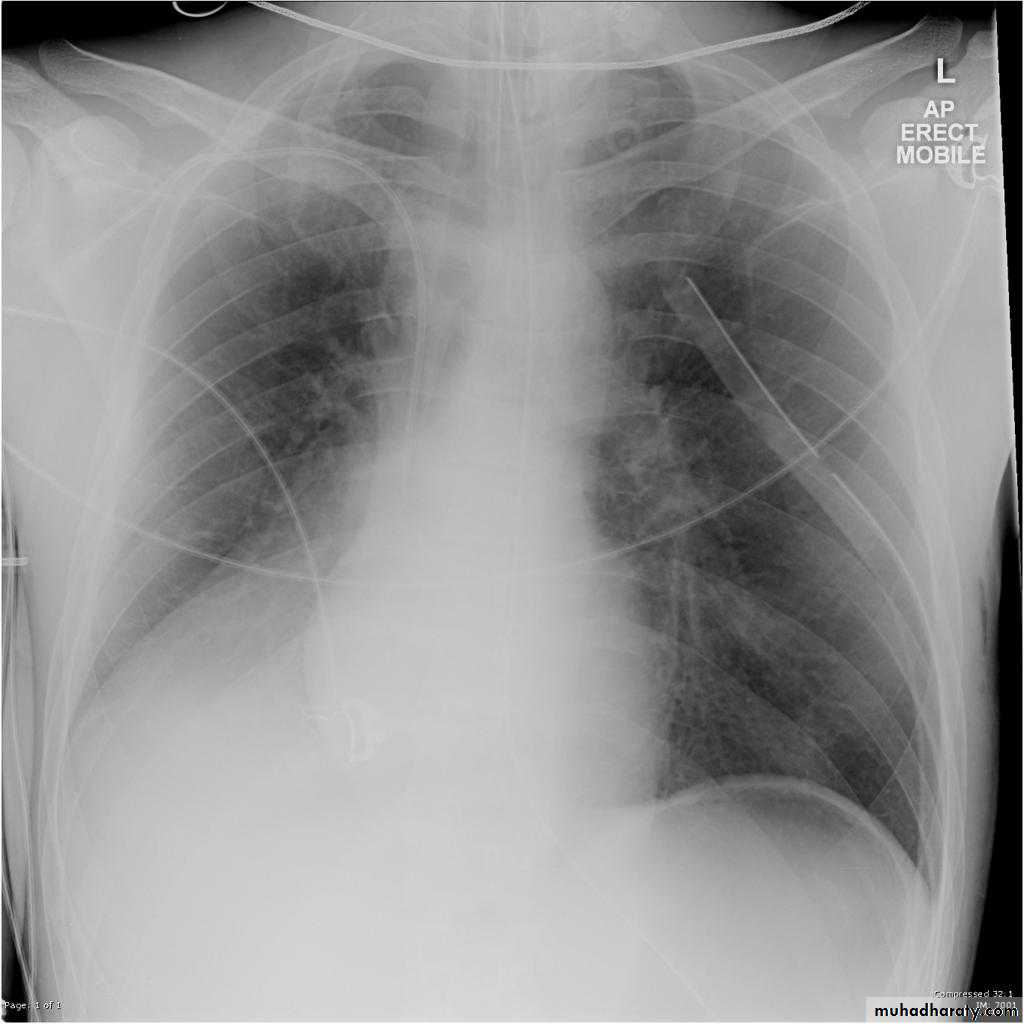

Left lower lobe collapse has distinctive features, and can be readily identified on frontal chest radiographs, provided attention is paid to the normal cardiomediastinal contours. The shadow cast by the heart does however make it harder to see than the right lower lobe collapse

Radiographic features

Left lower lobe collapse

is readily identified in a well penetrated film of a patient with normal sized heart, but can be challenging in the typical patient with collapse, namely unwell patients, with portable (AP) often under-penetrated films, often with concomitant cardiomegaly. Features to be observed include :

triangular opacity in the posteromedial aspect of the left lung

edge of collapsed lung may create a 'double cardiac contour'

left hilum will be depressed

loss of the normal left hemidaphgragmatic outline

loss of the outline of the descending aorta

Non-specific signs indicating left sided atelectasis are usually also be present including:

elevation of the hemidiaphragm

crowding of the left sided ribs

shift of the mediastinum to the left

chest X-ray

On lateral projection the left hemidiaphragmatic outline is lost posteriorly and the lower thoracic vertebrae appear denser than normal (they are usually more radiolucent than the upper vertebrae) .